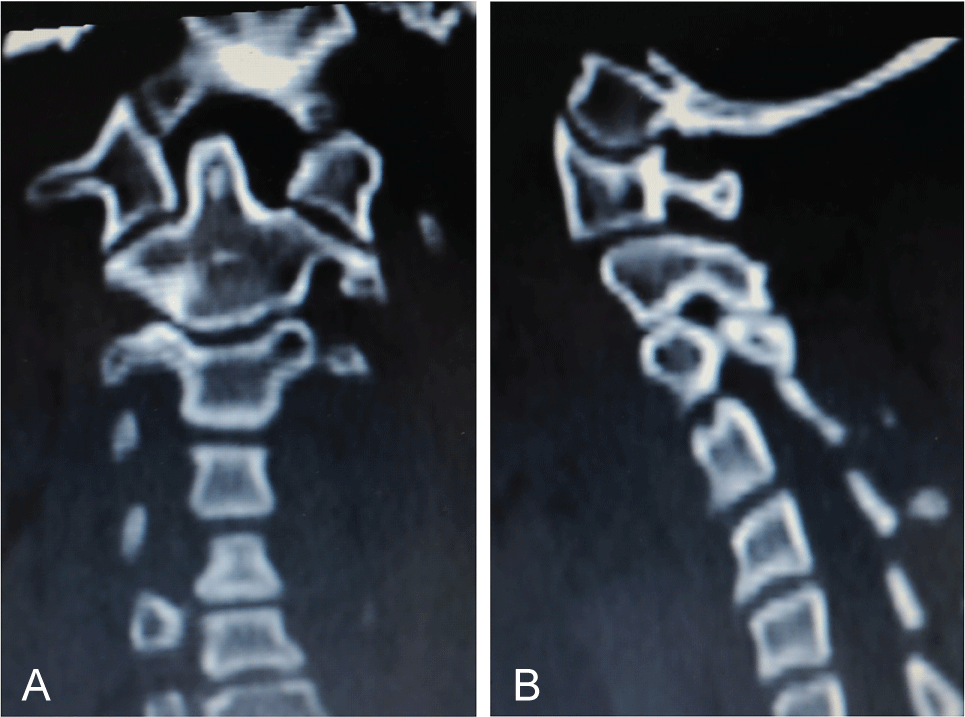

Figure 2: CT: a) Odontoid apophysis asymmetry and right anterior vertebral hemi-arch hypoplasia; b) Spinal canal asymmetry of vertebral posterior arches: Flattening on the right side and convexity on the left. View Figure 2

Figure 3: 2D CT: a) A coronal plane search found odontoid apophysis symmetry regarding lateral masses of the atlas; b) A sagittal plane search found an occipital condyle of normal morphology. View Figure 3

Figure 5: a) Postoperative CT (5 years follow-up); b) Persistent abnormal positions of odontoid apophysis and asymmetry of the posterior vertebral arches and cervical spinal canal. View Figure 5